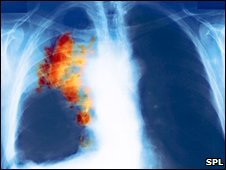

ریه

سرطان ریه از نوع "سلول کوچک" به سختی قابل تشخیص است

سرطان ریه یکی از کشنده ترین سرطان هاست و نوعی از آن که به "سلول کوچک" موسوم است و 20 درصد کل موارد این سرطان را تشکیل می دهد به سختی قابل تشخیص است. تنها 3 درصد بیماران مبتلا به این نوع سرطان ریه پنج سال دوام می آورند.